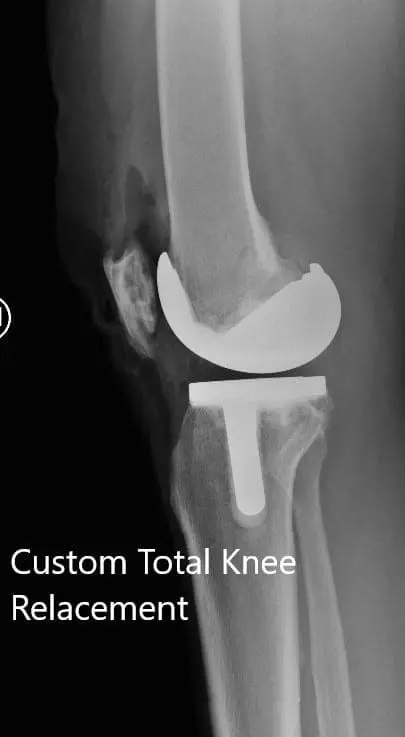

Postoperative X-ray showing the AP and lateral views of the left knee

Postoperative X-ray showing the AP and lateral views of the left knee - img 2

Postoperative X-ray showing the AP and lateral views of the left knee.